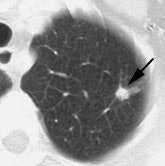

Example: The CT scan in this patient demonstrated a small nodule in the left upper lobe (black arrow). PET-FDG images demonstrate very intense accumulation of the tracer within the lesion (white arrow), which was a non-small cell lung cancer. (Case courtesy of H. Page McAdams MD, Department of Radiology, Duke University Medical Center) |